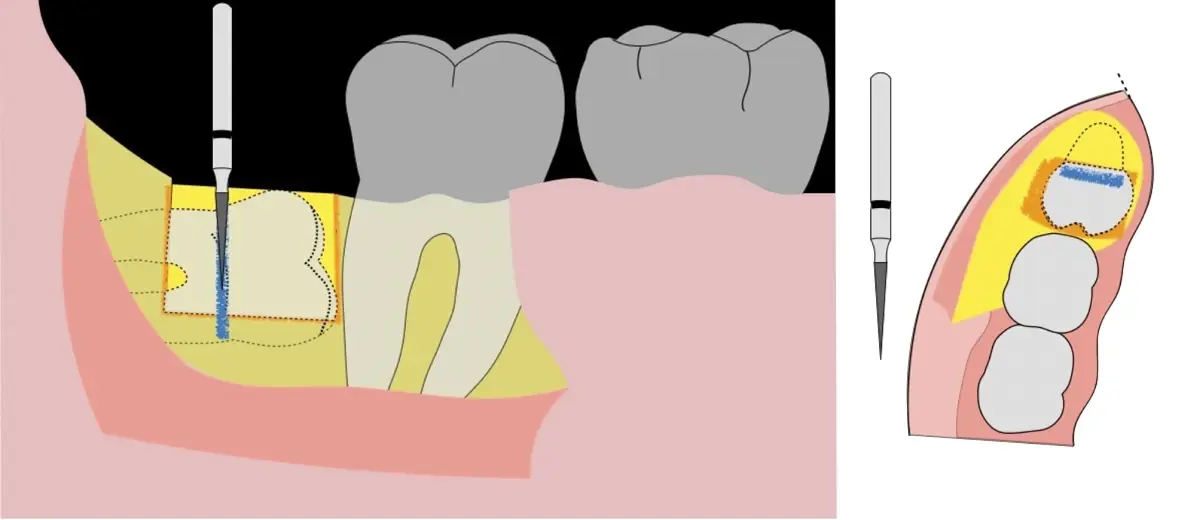

El procedimiento puede variar en su complejidad dependiendo de su ubicación, profundidad, angulación, y la densidad ósea circundante.2 Uno de los pasos más críticos y cruciales en la extracción es la osteotomía previa y concomitante al acceso quirúrgico del diente, para lo cual se utilizan diversos instrumentos como cinceles y martillos, instrumental rotatorio o de corte por ultrasonido.3

El instrumento piezoeléctrico utiliza un corte micrométrico que retira un área de superficie mínima de hueso, y reduce el riesgo de termonecrosis marginal en comparación con las fresas rotatorias convencionales.

En contraste, el instrumento piezoeléctrico utiliza un corte micrométrico que retira un área de superficie mínima de hueso, y reduce el riesgo de termonecrosis marginal en comparación con las fresas rotatorias convencionales.9 Los micromovimientos mejoran la precisión en el corte y el control táctil, y eliminan las macrovibraciones que se producen con los instrumentos rotatorios.10 Su frecuencia de oscilación es la amplitud de 60-200 μm horizontalmente y de 20-60 μm en sentido vertical, lo que es muy inferior en comparación con las micro sierras oscilantes; por lo tanto, proporciona cortes de osteotomía precisos y seguros. Adicionalmente, posee vibraciones ultrasónicas que descomponen el líquido de irrigación en partículas muy pequeñas (fenómeno de cavitación, que produce un efecto hemostático y así reduce la pérdida de sangre), lo que proporciona una visión clara y sin obstáculos del campo quirúrgico11,12.